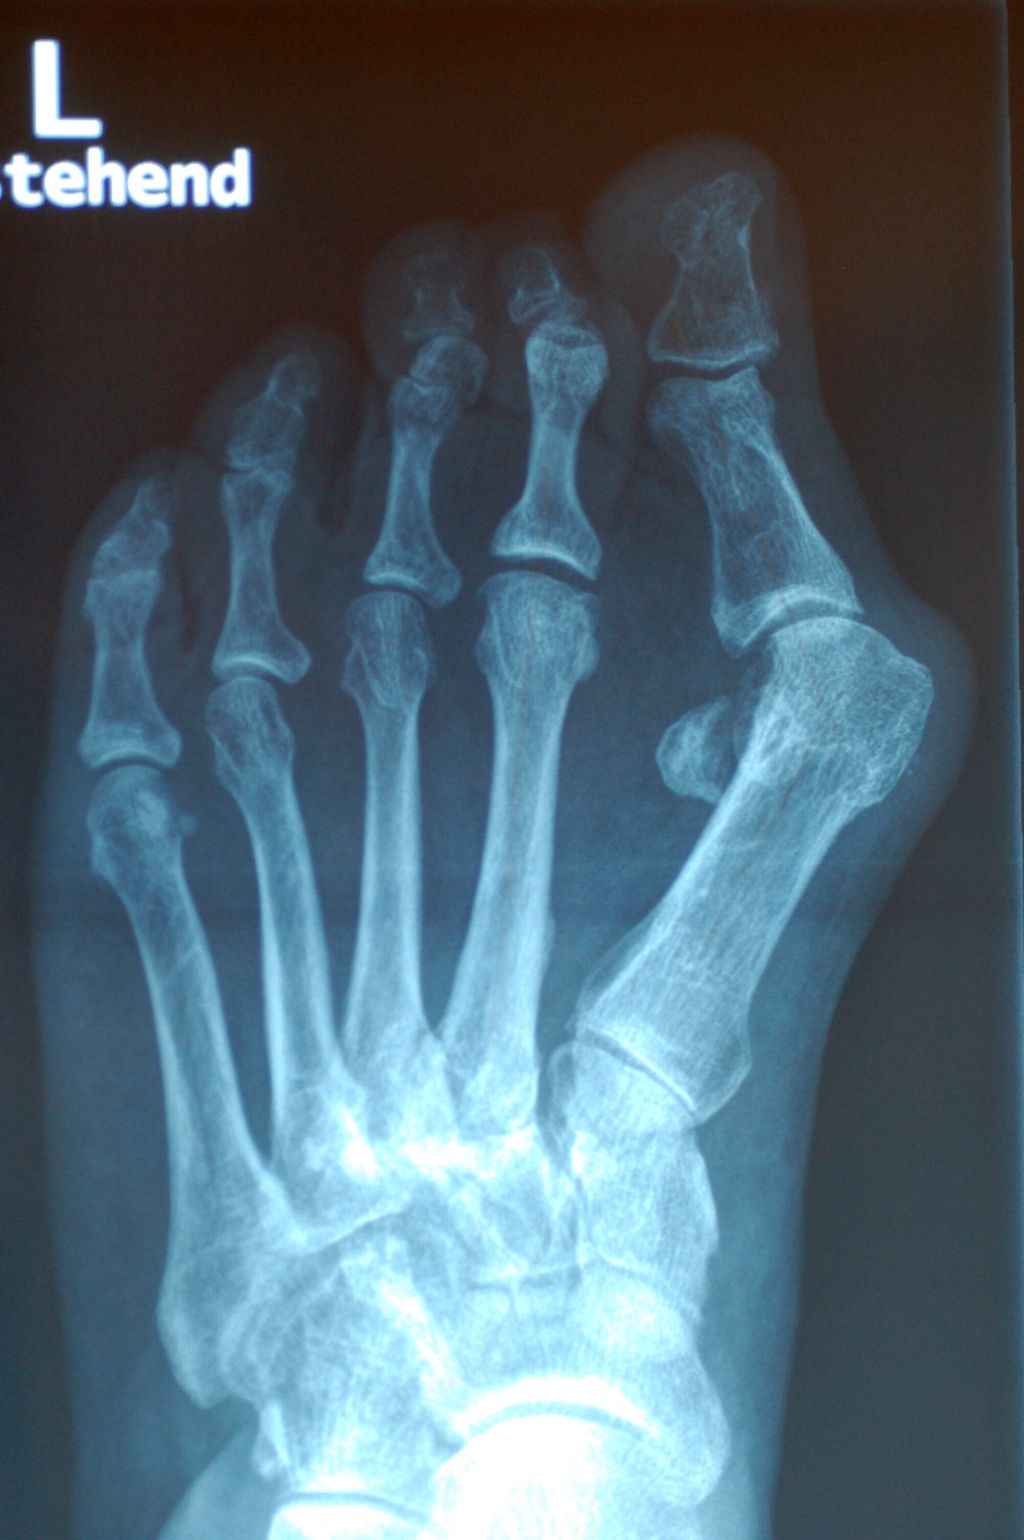

Abb. 1: Die Prominenz des Großzehenballens verstärkt sich erheblich aufgrund der M1-Pronation

Als komplexer pathologischer Prozess steht die M1-Pronation in engem Zusammenhang mit anderen Aspekten, nämlich dem HV-Winkel, dem Intermetatarsal(IM)-Winkel, einem abgeflachten Längsgewölbe und einer Hypermobilität. Eustace et al. zeigten 1994 einen signifikanten Zusammenhang zwischen der M1-Rotation und der Höhe des Längsgewölbes.7 Glasoe et al. vertreten ebenfalls die These, dass die Rotation des M1 von der Höhe des medialen Bogens abhängig ist.8 Sie konstatieren, dass bei abgeflachtem Längsgewölbe eine vermehrte Pronation im M1 stattfindet, bei erhöhtem mehr Supination. Mortier et al. beschreiben die typische Supination des M1 in der Allgemeinbevölkerung, wogegen bei HV-Deformitäten die typische Pronation des ersten Strahls zu beobachten ist.20 Dayton et al. fanden in ihrer Studie einheitlich pronierte M1-Positionen bei den untersuchten Füßen mit HV.4

Die Rolle des M1 besteht in Hinblick auf den Großzeh darin, dass eine übermäßige M1-Pronation ein Ungleichgewicht auf die Strukturen des Metatarsophalangeal-1-Gelenks bringt, die medialen Bänder überdehnt werden und das M1-Köpfchen nach medial gleitet (Abb.1). Die Position der Sesambeinchen lateralisiert sich. Entweder sie bleiben in ihren Gelenksflächen, gehalten von den medialen und lateralen metatarsophalangealen Ligamenten – Kim et al. nennen das „Pseudoluxation“ – oder sie subluxieren aus ihren Metatarsalköpfchenführungen.15 Dies ist die häufigere Variante (Abb.2).